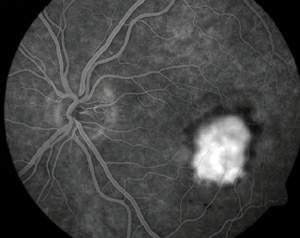

Picture of the fundus showing intermediate age-related macular degeneration.

يأمل الباحثون تطويرَ معالجات جديدة تستطيع إبطاء تقدم التنكس البقعي أو إيقافه. إن المَعْلم المميز للتنكّس البُقْعي هو فقدان الرؤية المركزية، غير أن مظهر الشبكية يختلف على نحو كبير من مريض إلى آخر. وفي معظم الأحيان، يرتبط المرض البقعي عند المسنين ـ الذي يُدعى الاعتلال البقعي المتعلق بالعمر age-related maculopathy (أو اختصارا ARM) ـ بفقدان في خلايا الظهارة RPE. فعندما يُنظر إلى الشبكية عبر منظار العين ophthalmoscope يظهر فقدان تلك الخلايا على شكل باحات غير مصطبغة، أو مصطبغة ولكن على نحو غير منتظم. ويمكن تعرف فقدان خلايا الظهارة RPE على نحو أكثر دقة بالتصوير الفلوروسيني (اللاّصِف) للأوعية fluorescein angiography، وهو تقنية تمكِّن أطباء العيون من رؤية الأوعية الدموية للعين بحقن مركب فلوروسيني في تيار الدم. ففي العين السوية يُرى الصباغ الفلوروسيني بسهولة في أوعية الدم الدقيقة ضمن الشبكية، غير أنه لا يُرى ـ أو يُرى بصعوبة كبيرة ـ في الأوعية المشيمانية الأكثر انتشارا؛ لأن هذه الأوعية تقع خلف الاصطباغ الثقيل للظهارة RPE. أما في عين مصابة بالاعتلال ARM فيظهر الصبغ داخل الدورة المشيمانية في أي باحة فقدت خلايا من الظهارة RPE.

إن تصوير الأوعية بالفلوروسين تقانة تتيح لأطباء العيون ملاحظة تأثيرات التنكس البقعي بحَقْن (زرق) صبغ فلوروسيني (لاصف) في تيار الدم. وبعد 12 ثانية تماما من الحقن يضيء الصبغ شرايين الشبكية، في حين تبقى الأوردة مظلمة (في اليمين). تظهر البقعة كمنطقة مظلمة بسبب نزيف سبق حدوثه من أوعية جديدة كانت اقتحمت المنطقة المركزية للشبكية. وبعد نصف دقيقة تغدو البقعة ساطعة بسبب الدم المصطبغ الذي رَشَح من الأوعية الجديدة إلى الشبكية (في اليسار).